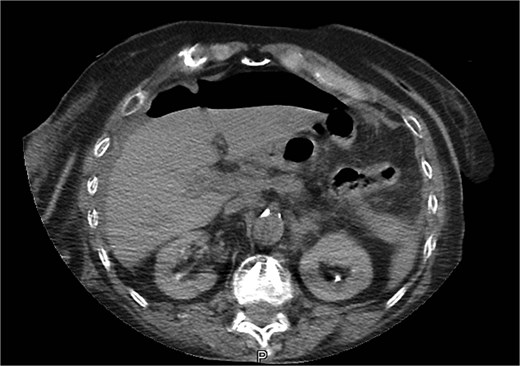

Due to persistent abdominal pain, a computed tomography scan of the abdomen was performed ~12 h after thrombolysis. The results showed a perforated gastric ulcer with free gas in the abdomen (Fig. 2). Emergency laparotomy revealed a perforated duodenal ulcer (PDU), just posterior to the pylorus, with total purulent peritonitis. Surgical treatment included excision of the ulcer and Mikulitz pyloroplasty with a Cellan-Jones patch. The procedure was completed with peritoneal lavage and drain placement.

An abdominal CT scan performed for persistent abdominal pain revealed free abdominal gas, and laparotomy revealed a PDU. Various techniques, both open and minimally invasive, can be used to repair a PDU [10, 11]. The proximity of the ulcer to the duodenum was the factor that led us to choose Mikulitz pyloroplasty for the patient. It is well established that systemic thrombolysis may increase the risk of postoperative bleeding at the surgical site and may be used outside the approved indications, but only after a risk–benefit assessment [3]. In this case, we chose to perform open reconstruction because of uncertainty regarding the timing of perforation and prior administration of thrombolysis. There were also concerns about bleeding control. The operation was uneventful and hemostasis was easily achieved. The estimated blood loss was <50 cc.